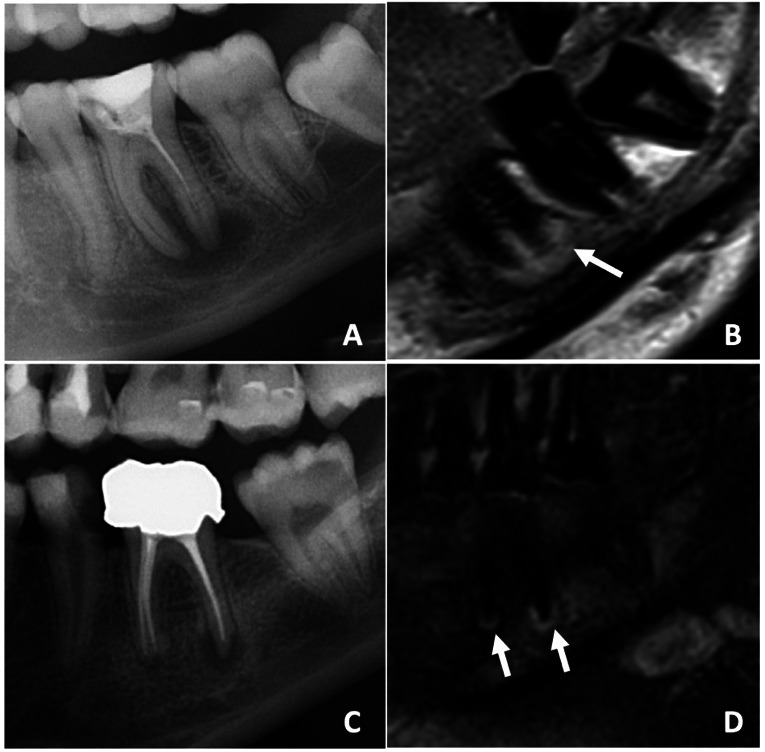

Abstract Image